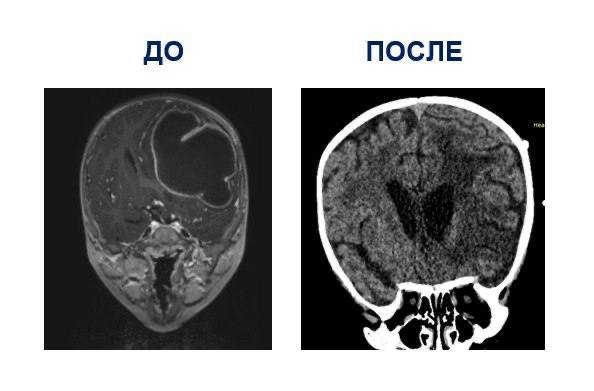

Врачи обнаружили у ребёнка крупный внутричерепной абсцесс объёмом более 80 мл. По словам нейрохирургов, он мог возникнуть из-за неправильно леченного отита. Без немедленной операции последствия были бы тяжёлыми — от повреждения мозга и паралича до эпилепсии и смертельного исхода.

Хирурги точно определили место абсцесса, вскрыли его, удалили гной и установили дренаж для оттока. Операция прошла успешно, и мальчика уже выписали домой.